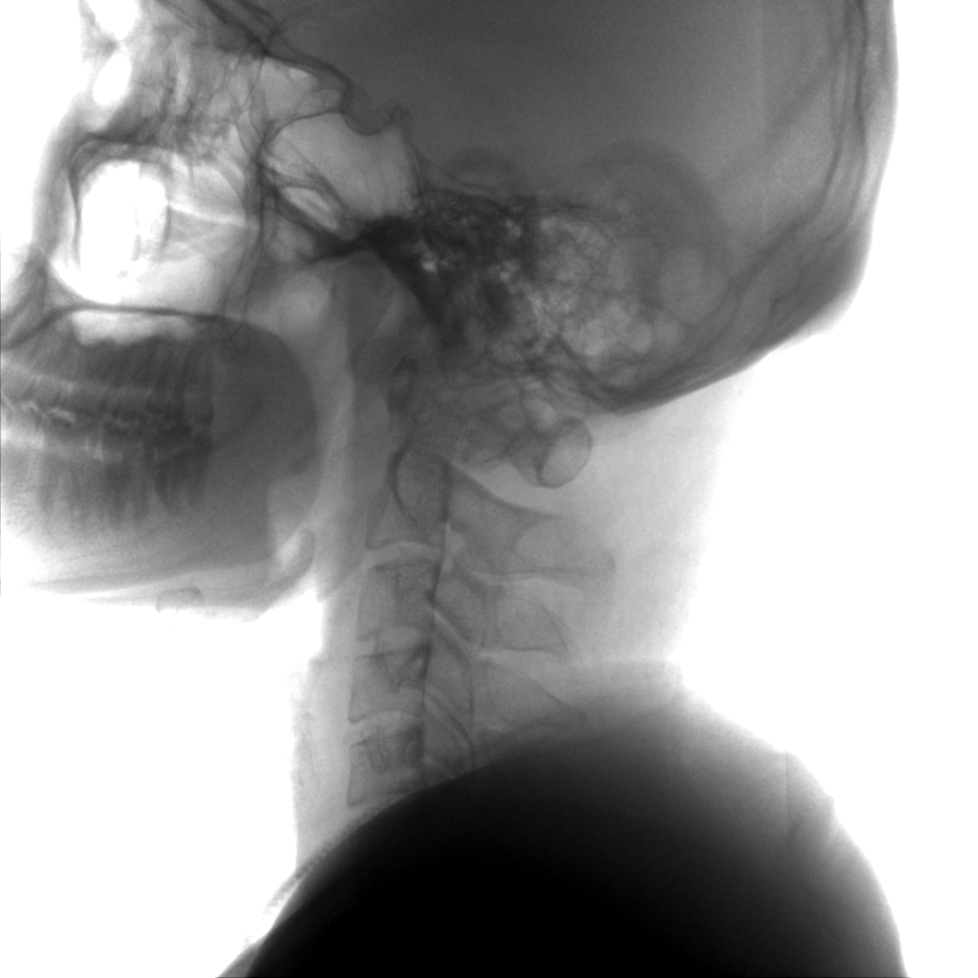

提供更大的术中三维成像视野,采集更多图像信息,可一次拍全全段颈椎、全段腰椎、七节胸椎、双侧骶髂关节、股骨头及单侧盆骨。